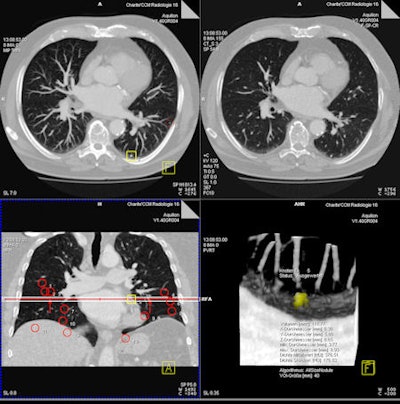

| Representative images of CT data analysis with CAD-2. The successful detection is presented in an axial maximum intensity projection (MIP) (upper left), in a thin-slice axial reconstruction (upper right), and as CAD marker in a coronal MIP (lower left), as well as in a volume-rendered view (lower right). |

Median false-positive rates per patient were five for CAD-1 versus six for CAD-2 with SD-CT. For ULD-CT, rates were eight for CAD-1 and three for CAD-2.

After separate statistical analysis of nodules with diameters of 5 mm and larger, detection rates increased to 83% for CAD-1 and 61% for CAD-2 at SD-CT and to 89% for CAD-1 and 67% for CAD-2 at ULD-CT. Overall, for both CAD systems, there were no significant differences between the detection rates for standard-dose and ultralow-dose datasets (p > 0.05).

Still, the number of false positives was highly variable by case, CAD system, and the use of standard or low-dose CT protocols.

"In case 21, CAD-1 found more than 25 false-positive nodules in a standard-dose CT scan," Romano said. "If we look at the ultra-low-dose results for CAD-2 [in the same case], there were absolutely no false-positive findings. In another example, there were more than 35 false-positive findings in CAD-1 in the ultra-low-dose dataset and only five false positives using standard dose for both CAD systems."

Differences between the systems could also be seen in the distribution of detected nodules, she said. "CAD-1 seemed to have more difficulties finding nodules close to the vessels, with 56% of the nodules missed," she said. CAD-2 had more difficulty finding nodules close to the pleural surface, with 42% missed nodules.